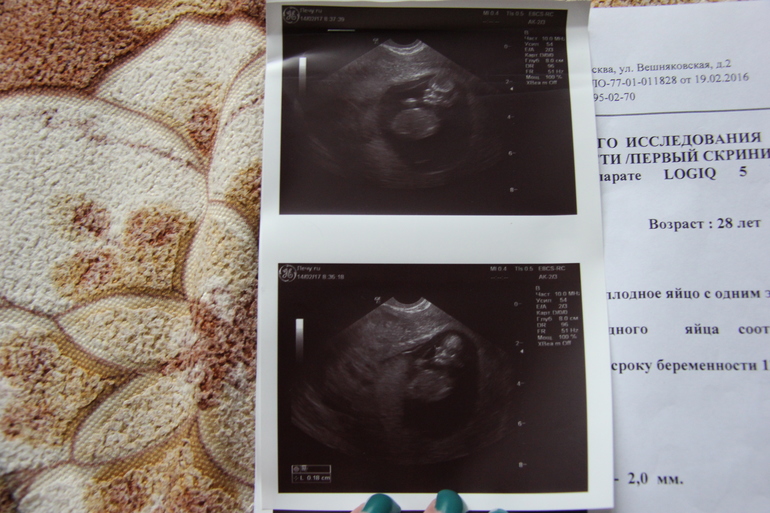

Вопросы про УЗИ, обследования и анализы: что, где, как, когда?Ходили на первый скрининг в 12 недель ровно...ТТТТ все у нас хорошо и мы растем и развиваемся.Только пока не знаем точно кто там...Муж мечтает о дочке..Но вроде похоже на мальчика..Хотя на таком сроке рано говорить...

У нас я так понимаю половая пренадлежность это второе фото...

Хотя точно не знаю...

, на этом сроке они обычно смотрят не снизу. как в 20 недель, а сбоку, потому как палочки и у девочек и у мальчиков есть, просто угол наклона разный)